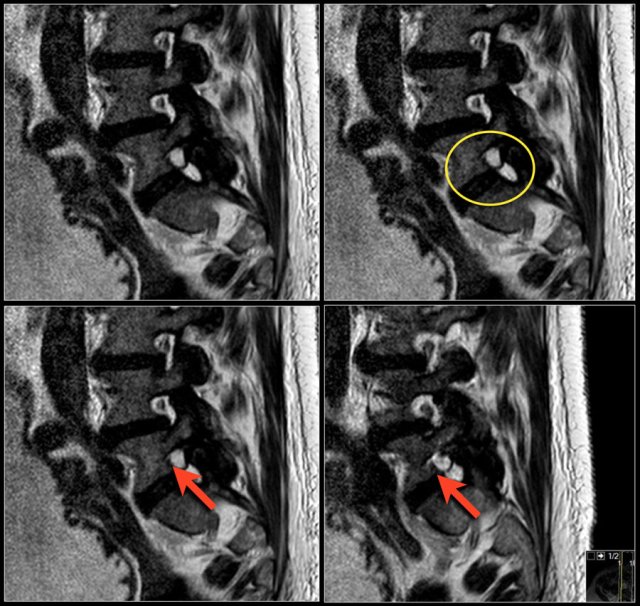

Synovial cysts can be easily overlooked.

On these T2W-images it looks as if the foramen is normal.

Notice that the nerve is missing.

In fact the neuroforamen is almost completely filled by the synovial cyst, which compresses the nerve root against the vertebra (arrows).

The nerve can hardly be seen.